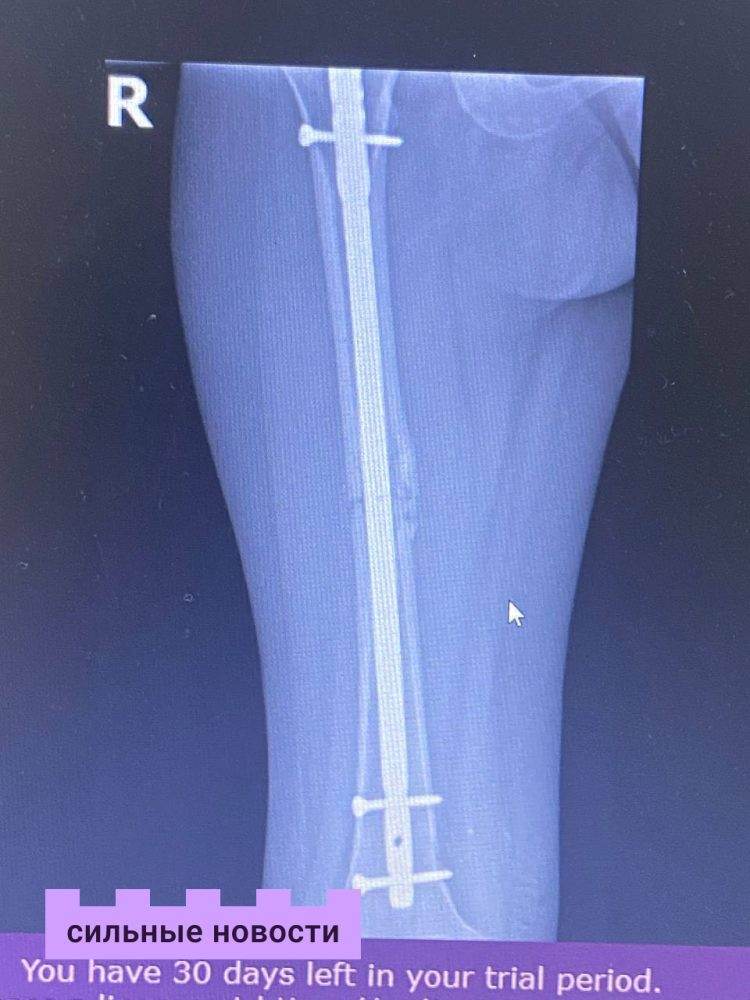

Ангелина согласилась на третий вариант: интрамедуллярный гвоздь с винтами. Он не восстановит полностью длину ноги, но с ним относительно быстро можно начинать ходить.

«В конце июля меня прооперировали под спинальным наркозом. Операция длилась 4 часа, и это была еще та пытка, но оно того стоило. Я слышала, как мне пилили кость, доставали старую металлоконструкцию, сверлили, били молотком, и все это всплывало перед глазами. Я человек, который теряет сознание даже от уколов, а тут такое… Всю операцию у меня была страшная истерика, но я довольна результатом. Теперь у меня ровная и красивая нога», – с радостью поделилась наша подписчица.

Вскоре у гомельчанки началась реабилитация: массаж, ЛФК, криотерапия и озокерит. И почти через 2 месяца девушке разрешили ходить. Небольшая хромота по-прежнему остается, но патологическая боль прошла.

«В свои 18 лет я учусь ходить в третий раз, что на самом деле очень грустно. За этот год мышцы моей ноги сдулись, и вроде как, именно это является главной причиной моей неровной походки. Доктор сказал, что у меня положительный симптом Тренделенбурга, и исправить походку возможно. Сейчас я активно занимаюсь своим восстановлением, а еще начала снимать видео в TikTok, в которых рассказываю свою историю. Благодаря этому я нашла большое количество людей, оказавшихся в подобной ситуации. Мы общаемся, поддерживаем друг друга и делимся позитивом», – рассказала Ангелина.